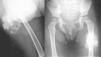

En la radiografía simple se aprecia una tumoración de partes blandas bien delimitada, de unos 8 x 5cm, con múltiples calcificaciones groseras internas (Figura 1).

Figura 1.